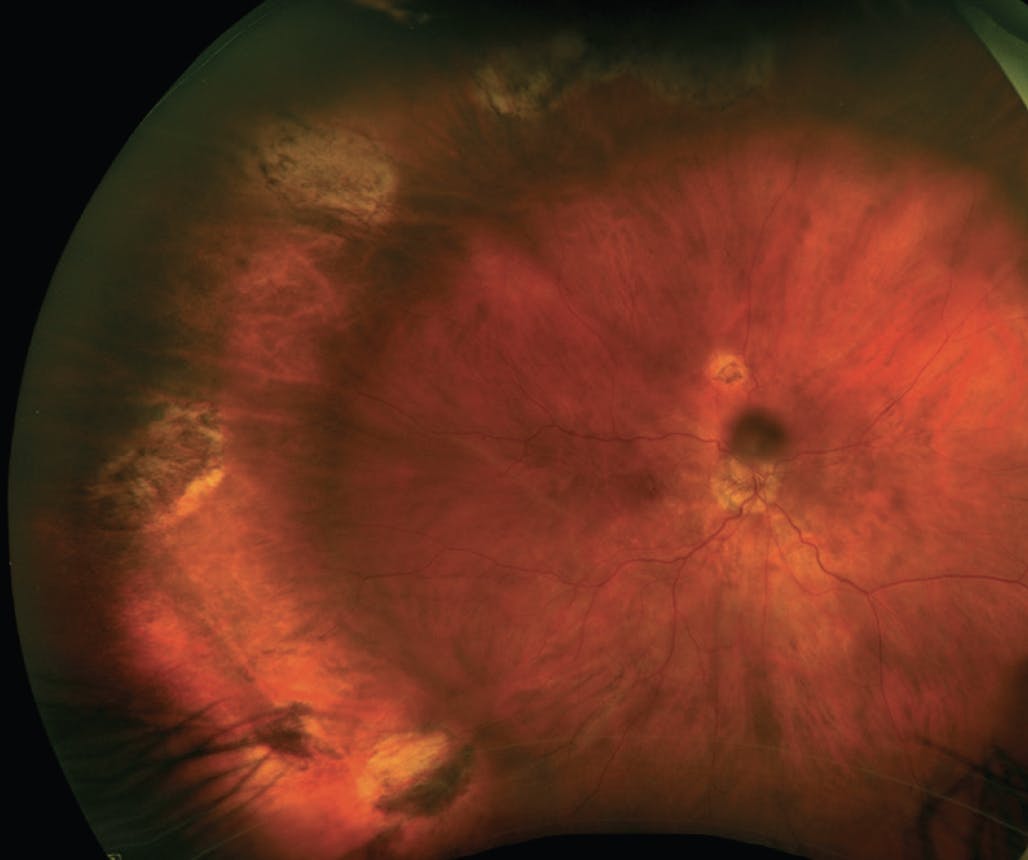

Salabati et al recently published a study of 389 eyes that evaluated SSAS rates for primary RRD repair in eyes with high-risk features for PVR.3 Eyes were deemed high-risk if they had at least one of the following risk factors: preoperative PVR grade A or B, vitreous hemorrhage, RRD involving 50% or more of the retinal area, presence of three or more retinal breaks, history of prior cryotherapy, presence of choroidal detachment, and/or duration of RRD greater than 2 weeks. Choice of surgical technique was pars plana vitrectomy (PPV) in 67.9% of eyes and combined PPV with scleral buckling (SB) in 32.1% of eyes. Overall, the SSAS rate was 71.5% at 3 months after surgery. When comparing surgical techniques, the SSAS rate was significantly higher in eyes treated with PPV/SB compared with PPV alone (80.8% vs 67%, P = .006). This higher SSAS was noted even in eyes treated with PPV/SB that were more likely to be macula-off and have a greater extent of RRD compared with eyes in the PPV only group (Figure 2).3

Figure 2. A high-risk RD was repaired with PPV and SB. The initial detachment was macula-off with 8 clock hours of detachment. Note the multiple breaks treated with laser retinopexy temporally.

The authors completed a multivariate analysis to assess the effect of the various risk factors on SSAS. However, no individual risk factor was significantly associated with the rate. Notably, use of PPV/SB was the only feature associated with SSAS (odds ratio [OR] = 2.04, P = .019).

The relatively lower SSAS rate of 71.5% observed in eyes with RRD and high-risk features, compared with the 88% to 90% rate reported in other large series of primary RRD,4-6 suggests these risk factors remain clinically relevant. Given the significantly higher SSAS rate with PPV/SB observed in this study, use of PPV/SB in eyes with primary RRD and high-risk features may be advised. Additional study of this high-risk cohort is of interest and may be a study population worth including in future clinical trials for PVR.